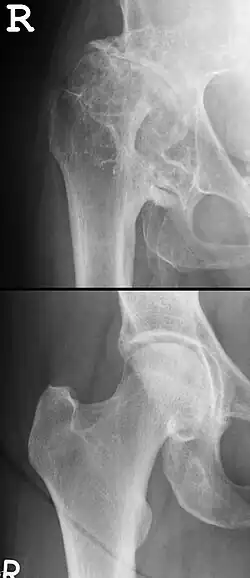

Osteophyten (von altgriechisch ὀστέον ‚Knochen‘ und φυτόν ‚Gewächs‘), auch Exophyten genannt, sind degenerative, strukturelle Veränderungen in Form von knöchernen Ausläufern am Rand des Knochens. Diese Knochenneubildungen, die sich als Knochenvorsprünge am Rande der Gelenkflächen bilden können, können in Form von Spangen, Randzacken, Höckern oder flächenhaften Auflagerungen auftreten. Die Bildung von Osteophyten ist ein fehllaufender Versuch des Körpers, die Auflagefläche eines arthrotischen Gelenkes zu verbreitern und damit den Auflagedruck zu mindern. Sie treten im Stadium 4 von arthrotischen Gelenkveränderungen auf.[2] Am Knie spricht man von Konsolenbildung, an der Wirbelsäule von Spondylophyten oder Syndesmophyten (siehe auch Osteochondrosis intervertebralis). Osteophyten schränken, wenn sie in Bewegungsrichtung liegen, die Beweglichkeit ein. Sie können auch durch Druck auf Nerven und andere Weichteile zu Schmerzen und weiteren Schäden führen. Differentialdiagnostisch muss man sie von Exostosen abgrenzen.[3]

Diagnostik

Osteophyten sind im Röntgenbild sowie sonografisch nachweisbar.[6] Sie gelten als Zeichen einer fortgeschrittenen Arthrose.